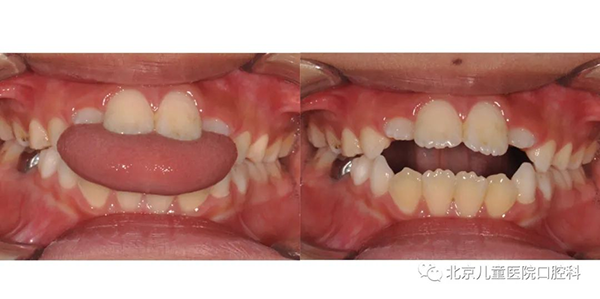

有的孩子存在一些口腔不良习惯,会影响牙齿的咬合和面部美观,比如口呼吸会导致下颌逐渐后缩、上牙逐渐前突;吐舌习惯会让牙齿前牙开咬,影响进食和发音。

口呼吸习惯导致下颌后缩、上牙前突

吐舌习惯导致前牙开合咬不上